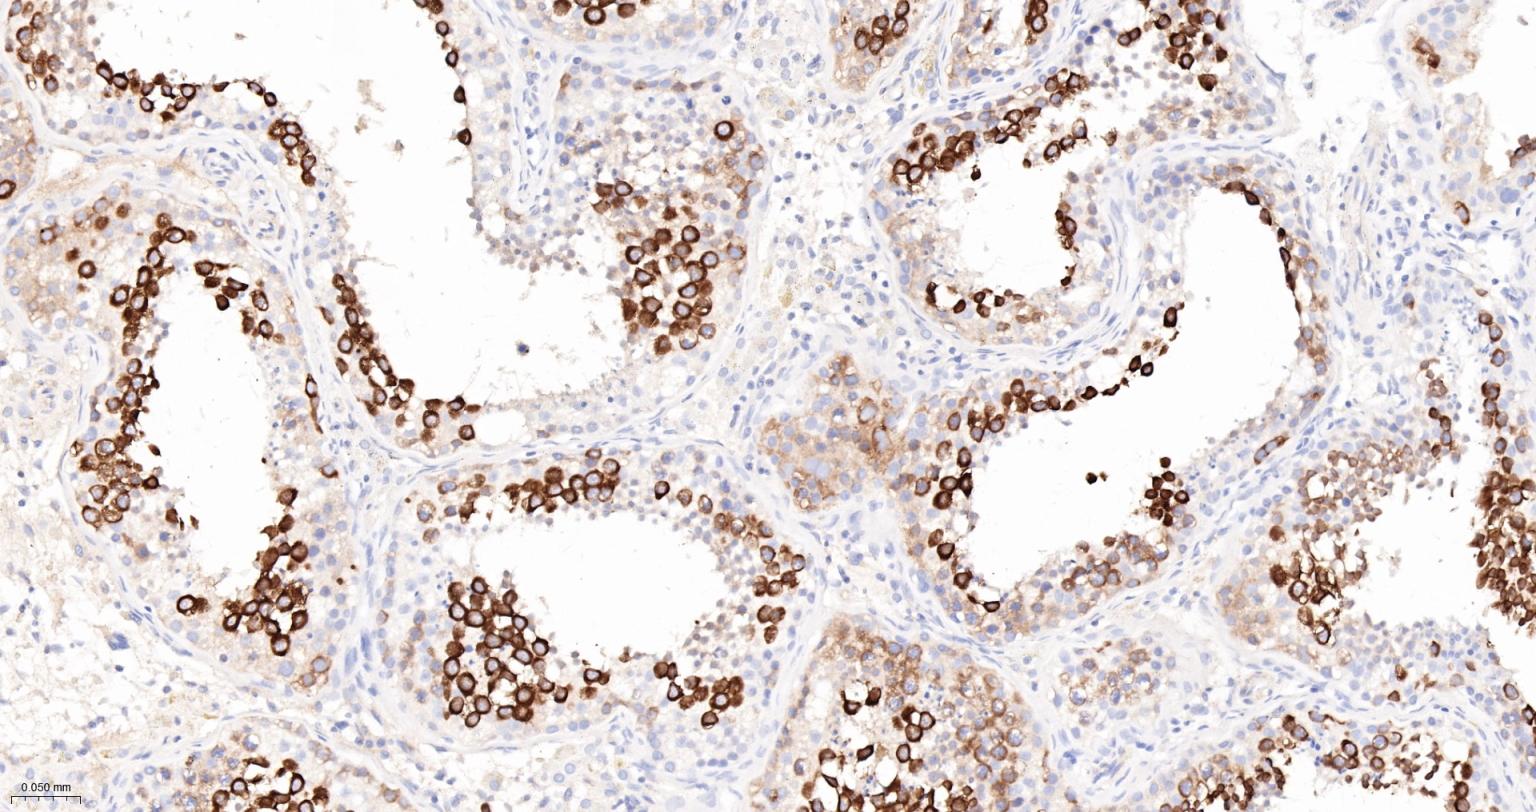

Paraformaldehyde-fixed, paraffin embedded Mouse Testicles; Antigen retrieval by boiling in sodium citrate buffer (pH6.0) for 15 min; The section was incubated with TACC3 Monoclonal Antibody, Unconjugated (bsm-61119R) at 1:200 overnight at 4°C, followed by conjugation to the bs-0295G-HRP and DAB (C-0010) staining.